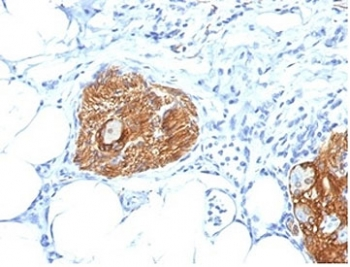

| Description | Mouse monoclonal antibody to CD56 (NCAM1) |

| Tested applications | IHC, WB |

| Dilution range | WB 1:2000, IHC 1:150 |

| Target | CD56 |